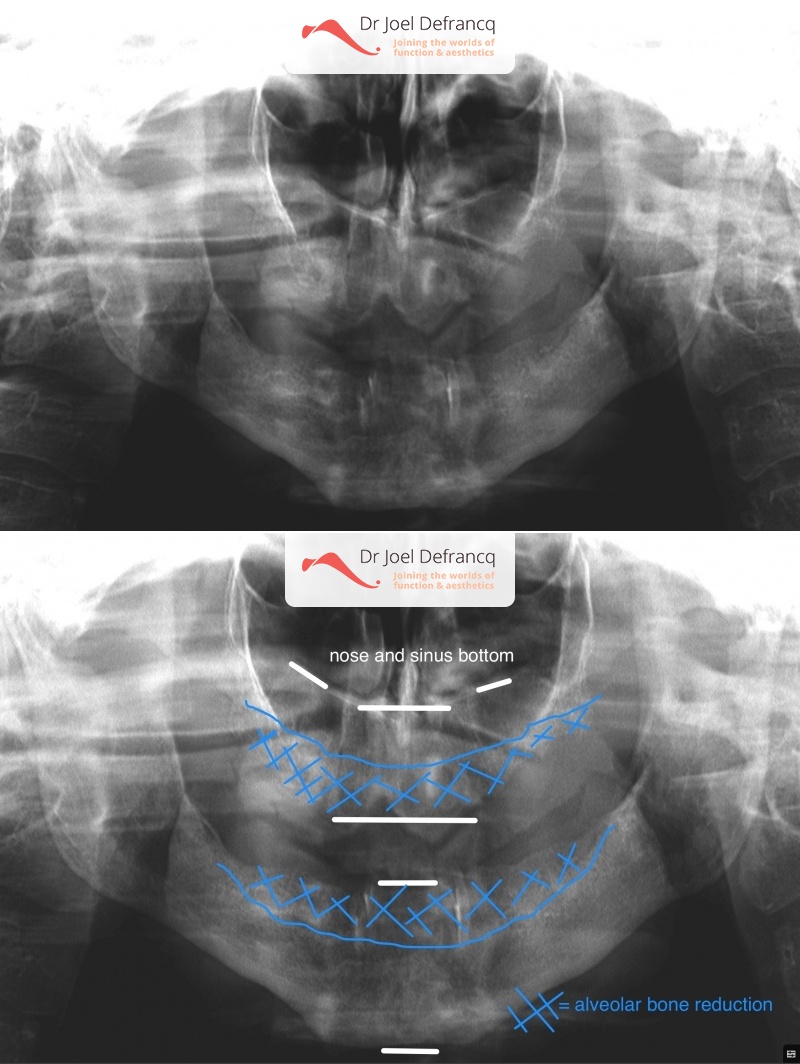

Kaakchirurgie

- Vertikale verkorting bovenkaak (Le Fort I)

- Implantaten met osteotomie